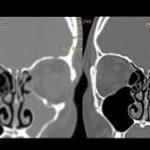

- Periodontal cep oluşumu ve kemik kaybı, dişetinin diş kökü üzerinden geri çekilmesini kolaylaştırır.

- İlerleyen vakalarda periodontal cerrahi, dişeti greftleri ve flep operasyonları uygulanabilir.

- Açığa çıkan diş kökü kapatılarak hem estetik hem fonksiyonel iyileşme sağlanır.